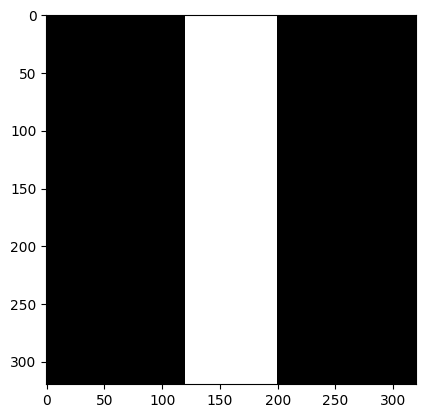

We consider the following two inverse problems: (i) Superresolution (SR), consisting of reconstructing a sharp image from measurements containing only the central low frequencies obtained by using the mask as in Fig. 2 (a & c); and (ii) Dealiasing, in which the obtained mask results in an aliasing artifact due to a coarser sampling in the phase-encoding direction. We use the masks displayed in Fig. 2(b & d). The inverse problem consists of restoring a finer sampling grid in the phase-encoding direction. Throughout the paper, we denote the experiments specifying the task name (one of the two tasks above) and the acceleration factor.

| (a) SR 4 | (b) Dealiasing 4 | (c) SR 8 | (d) Dealiasing 8 |